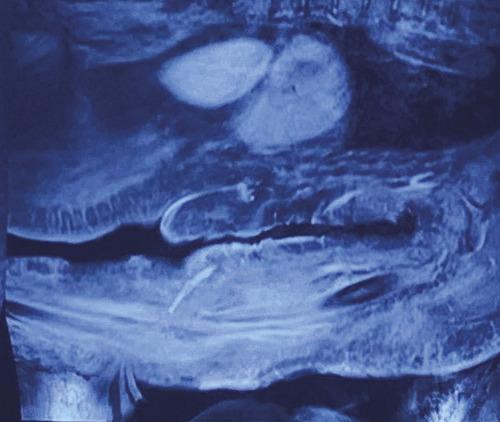

Après quelques jours de traitement immunosuppresseur, une douleur intense et insomniante s’installe, avec érythème et tuméfaction du membre supérieur gauche. Les examens complémentaires retrouvent une protéine C-réactive (CRP) à 300 mg/L, des hémocultures stériles, une échographie Doppler artérioveineuse sans thrombose. Le diagnostic d’une dermohypodermite bactérienne non nécrosante est évoqué dans un premier temps. La patiente est alors traitée par antibiothérapie (amoxicilline et acide clavulanique). L’évolution est défavorable, avec apparition de lésions nécrotico-hémorragiques rapidement extensives (fig. 2 ). Une imagerie par résonance magnétique (IRM) [fig. 3 ] montre une infiltration des parties molles sous-cutanées, des loges musculaires associées à des bulles d’air, en faveur d’une fasciite nécrosante. Une exploration chirurgicale permet de réaliser des biopsies profondes au niveau du fascia et du muscle. Le résultat histologique, après coloration de Grocott, montre une cryptococcose avec multiples foyers de nécrose de liquéfaction (fig. 4 ). Le diagnostic de fasciite nécrosante cryptococcique est finalement retenu. La recherche de l’antigène sérique cryptococique est positive (1 : 2 000, test d’agglutination au latex). La sérologie VIH (virus de l’immunodéficience humaine) est négative. À défaut d’amphotéricine B, du fluconazole à la dose de 400 mg/j est administré. L’évolution a été défavorable, avec décès à la suite d’un choc septique.

Après quelques jours de traitement immunosuppresseur, une douleur intense et insomniante s’installe, avec érythème et tuméfaction du membre supérieur gauche. Les examens complémentaires retrouvent une protéine C-réactive (CRP) à 300 mg/L, des hémocultures stériles, une échographie Doppler artérioveineuse sans thrombose. Le diagnostic d’une dermohypodermite bactérienne non nécrosante est évoqué dans un premier temps. La patiente est alors traitée par antibiothérapie (amoxicilline et acide clavulanique). L’évolution est défavorable, avec apparition de lésions nécrotico-hémorragiques rapidement extensives (